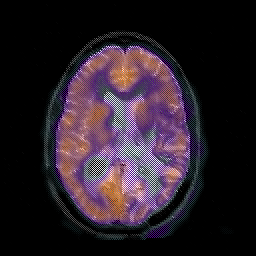

Glioblastoma multiforme overlay -- Slice #31

[Home][Help][Clinical][Tour 1][Tour 2][Tour 3] Slice 31